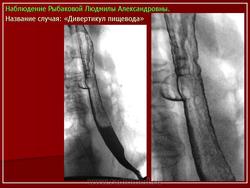

Клиническая картина, предварительный диагноз У большинства больных, особенно с небольшими дивертикулами, стойкие симптомы заболевания могут отсутствовать. Лишь эпизодически возникает дисфагия, чаще при поспешной еде, еде всухомятку. При дивертикулах больших размеров дисфагия возникает почти при каждом приеме пищи, в положении лежа может наблюдаться регургитация (обратное затекание) содержимого дивертикула в пищевод и глотку, срыгивание. Эти больные могут отмечать неприятный запах (вследствие разложения задержавшихся в пищеводе пищевых остатков). Основное значение для диагностики дивертикула имеет контрастное рентгенологическое исследование, при котором устанавливают дивертикул, определяют его размеры, форму, наличие или отсутствие в нем контрастной массы и пищевых остатков. Небольшие дивертикулы средней и нижней трети пищевода, в которых не задерживается контрастная масса, лучше выявляются при рентгенологическом исследовании пищевода в положении больного лежа. Небольшие бессимптомно протекающие дивертикулы часто являются случайной рентгенологической находкой при контрастном рентгенологическом исследовании, проводимом по другому поводу. Дивертикулы, соединяющиеся с пищеводом широким сообщением, выявляют при эзофагоскопии. Со временем дивертикулы нередко увеличиваются в размерах. При плохом опорожнении дивертикула (при мешкообразной форме, с дном, расположенным значительно ниже шейки дивертикула) в нем задерживается пища (особенно плохо разжеванные куски), которая может разлагаться; велика опасность возникновения дивертикулита, а затем - медиастинита. В дивертикулите могут задерживаться и проглоченные инородные тела (кусочки куриной или рыбьей кости и др.).

У большинства больных, особенно с небольшими дивертикулами, стойкие симптомы заболевания могут отсутствовать. Лишь эпизодически возникает дисфагия, чаще при поспешной еде, еде всухомятку. При дивертикулах больших размеров дисфагия возникает почти при каждом приеме пищи, в положении лежа может наблюдаться регургитация (обратное затекание) содержимого дивертикула в пищевод и глотку, срыгивание. Эти больные могут отмечать неприятный запах (вследствие разложения задержавшихся в пищеводе пищевых остатков). Основное значение для диагностики дивертикула имеет контрастное рентгенологическое исследование, при котором устанавливают дивертикул, определяют его размеры, форму, наличие или отсутствие в нем контрастной массы и пищевых остатков. Небольшие дивертикулы средней и нижней трети пищевода, в которых не задерживается контрастная масса, лучше выявляются при рентгенологическом исследовании пищевода в положении больного лежа. Небольшие бессимптомно протекающие дивертикулы часто являются случайной рентгенологической находкой при контрастном рентгенологическом исследовании, проводимом по другому поводу. Дивертикулы, соединяющиеся с пищеводом широким сообщением, выявляют при эзофагоскопии. Со временем дивертикулы нередко увеличиваются в размерах. При плохом опорожнении дивертикула (при мешкообразной форме, с дном, расположенным значительно ниже шейки дивертикула) в нем задерживается пища (особенно плохо разжеванные куски), которая может разлагаться; велика опасность возникновения дивертикулита, а затем - медиастинита. В дивертикулите могут задерживаться и проглоченные инородные тела (кусочки куриной или рыбьей кости и др.).

Наддиафрагмальный дивертикул